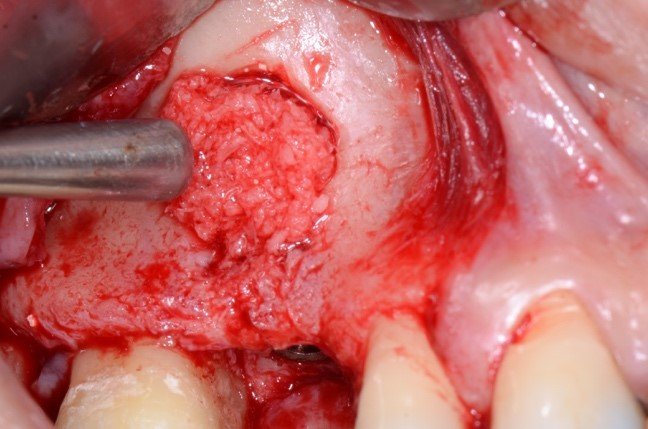

A irrigação da maxila é realizada por ramos de 2 principais vasos, a artéria alveolar superior posterior (AAPS) e a artéria infra-orbital (AIO), ramos da artéria maxilar 3,4. No estudo com tomografias de Khojastehpour et al 5 em 2016, eles encontraram anastomose na membrana entre as artérias AAPS e a AIO em 49.8% dos indivíduos, e do ponto de vista técnico nesssa condição, somente em casos de acidentes com rompimento da membrana sinusal poderia ocorrer hemorragias relevantes. Por outro lado, outros autores têm encontrado maior número de situações em que a AAPS se encontra intra-óssea, como nos estudos de Güncü et al 6 em 2011, e Ilgüi et al 7 em 2013, que observaram 68.2% e 71.1%, respectivamente. Quando a AAPS se encontra nessa última condição relatada, ocorre maior risco de dano vascular com hemorragia, especialmente se o canal vascular intra-ósseo for maior que 1 mm de espessura. Em média, alguns estudos têm demonstrado que a distância vertical do canal vascular da AAPS se apresenta próximo de 16 mm 5,7. Porém em casos de reabsorção do rebordo alveolar essa altura pode ser encontrada próximo de 11mm, segundo Rosano et al 4. A recomendação da tomografia como imagem de diagnóstico para identificação e mensuração da AAPS, pode estabelecer modificações estratégicas tanto na osteotomia, em relação ao desenho vertical e comprimento do implante, quanto na metodologia de instrumentação óssea. Podem ser usadas, por exemplo, ponteiras piezoelétricas sob irrigação para melhorar a visualização operatória e diminuir o risco de laceração vascular. As figuras de 1 a 12, demonstram caso clínico de técnica cirúrgica com osteotomia modificada, usando unidade piezo Mectron para remoção da parede lateral e preservar a AAPS, que foi diagnosticada em exame tomográfico durante a fase pré-operatória.

As figuras 16 e 17 mostram o transoperatório de um caso de hemorragia após dano a AAPS durante procedimento de osteotomia para rotação superior da janela óssea. A hemorragia durante a cirurgia trouxe dificuldades na visualização da membrana e a mobilização da janela para o interior da cavidade para formar o teto sobre a membrana sinusal. Somente após o preenchimento total com enxerto ósseo bovino particulado e cobertura com membrana hemostática de colágeno, houve diminuição do fluxo sanguíneo local. Mesmo com a manobra transoperatória, ocorreu a formação de extenso blefarohematoma periorbital e hematoma cérvico-facial. Segundo relato da paciente, o edema palpebral e na região parotídeo-masseterina provocaram dificuldade na abertura palpebral e bucal. As figuras 18 e 19 demonstram os hematomas já em regressão no 110 dia de pós-operatório (PO), já em uso de compressas mornas desde o 70 dia de PO, associado a moderada massagem local para drenagem hemo-linfática nos tecidos com pomada fibrinolítica.